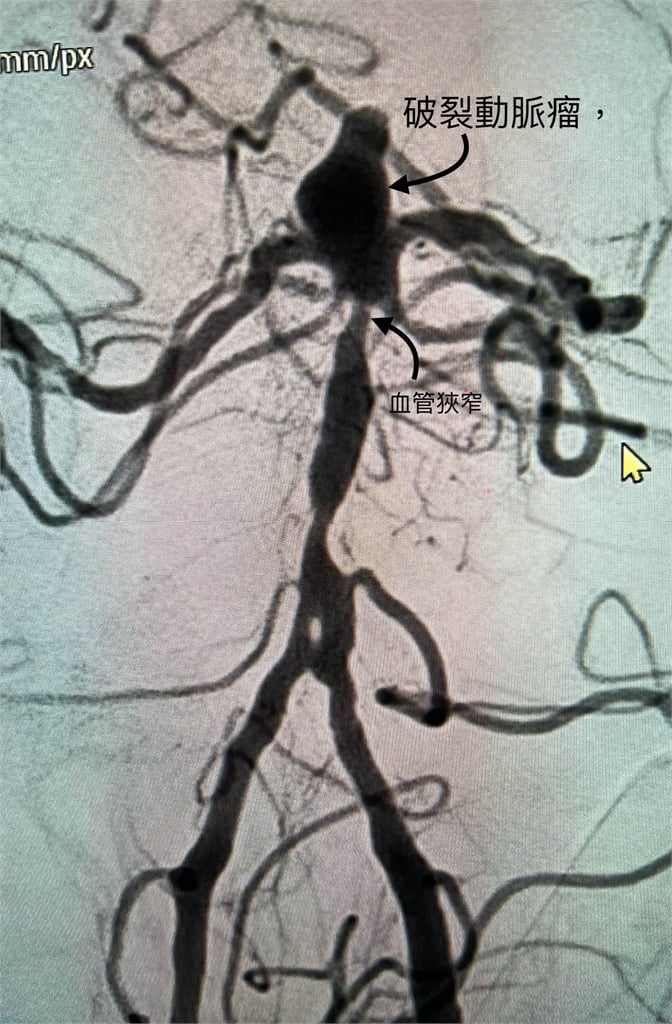

陳啟仁也分享近期急診處理的真實案例,一名患者因動脈瘤破裂送醫,出血衝力甚至穿破第三腦室底板,導致腦室積血與水腦。檢查發現,是一顆7毫米的基底動脈頂端動脈瘤破裂,加上近端血管狹窄,讓血流速度進一步升高,更容易把血管壁沖破。動脈瘤本身並不是腫瘤,而是血管膨出,多與動脈硬化有關,而高血壓、高血脂、糖尿病、抽菸與遺傳都是關鍵因素。陳啟仁再次提醒,天冷時一定要做好保暖,尤其頭部與頸部要戴帽子、圍巾,別讓血管在低溫下承受過大壓力。